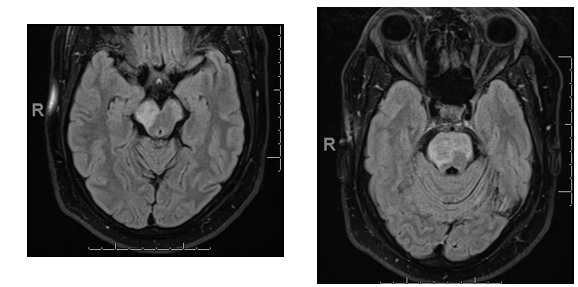

45 year old man, seen in the emergency room with recent onset of apparent seizures involving the left side of the body. History of hypertension and diabetes.

Stereotyped movements involving the left side of the body, including the face, and occurring currently throughout the day (20-30 times).

There was no associated loss of consciousness and no aura present. No history of epilepsy in the family. Not brought out, or worsened by movement. Resolved rapidly with phenytoin.

MRI show hyperintense signal in midbrain and pons on FLAIR images: